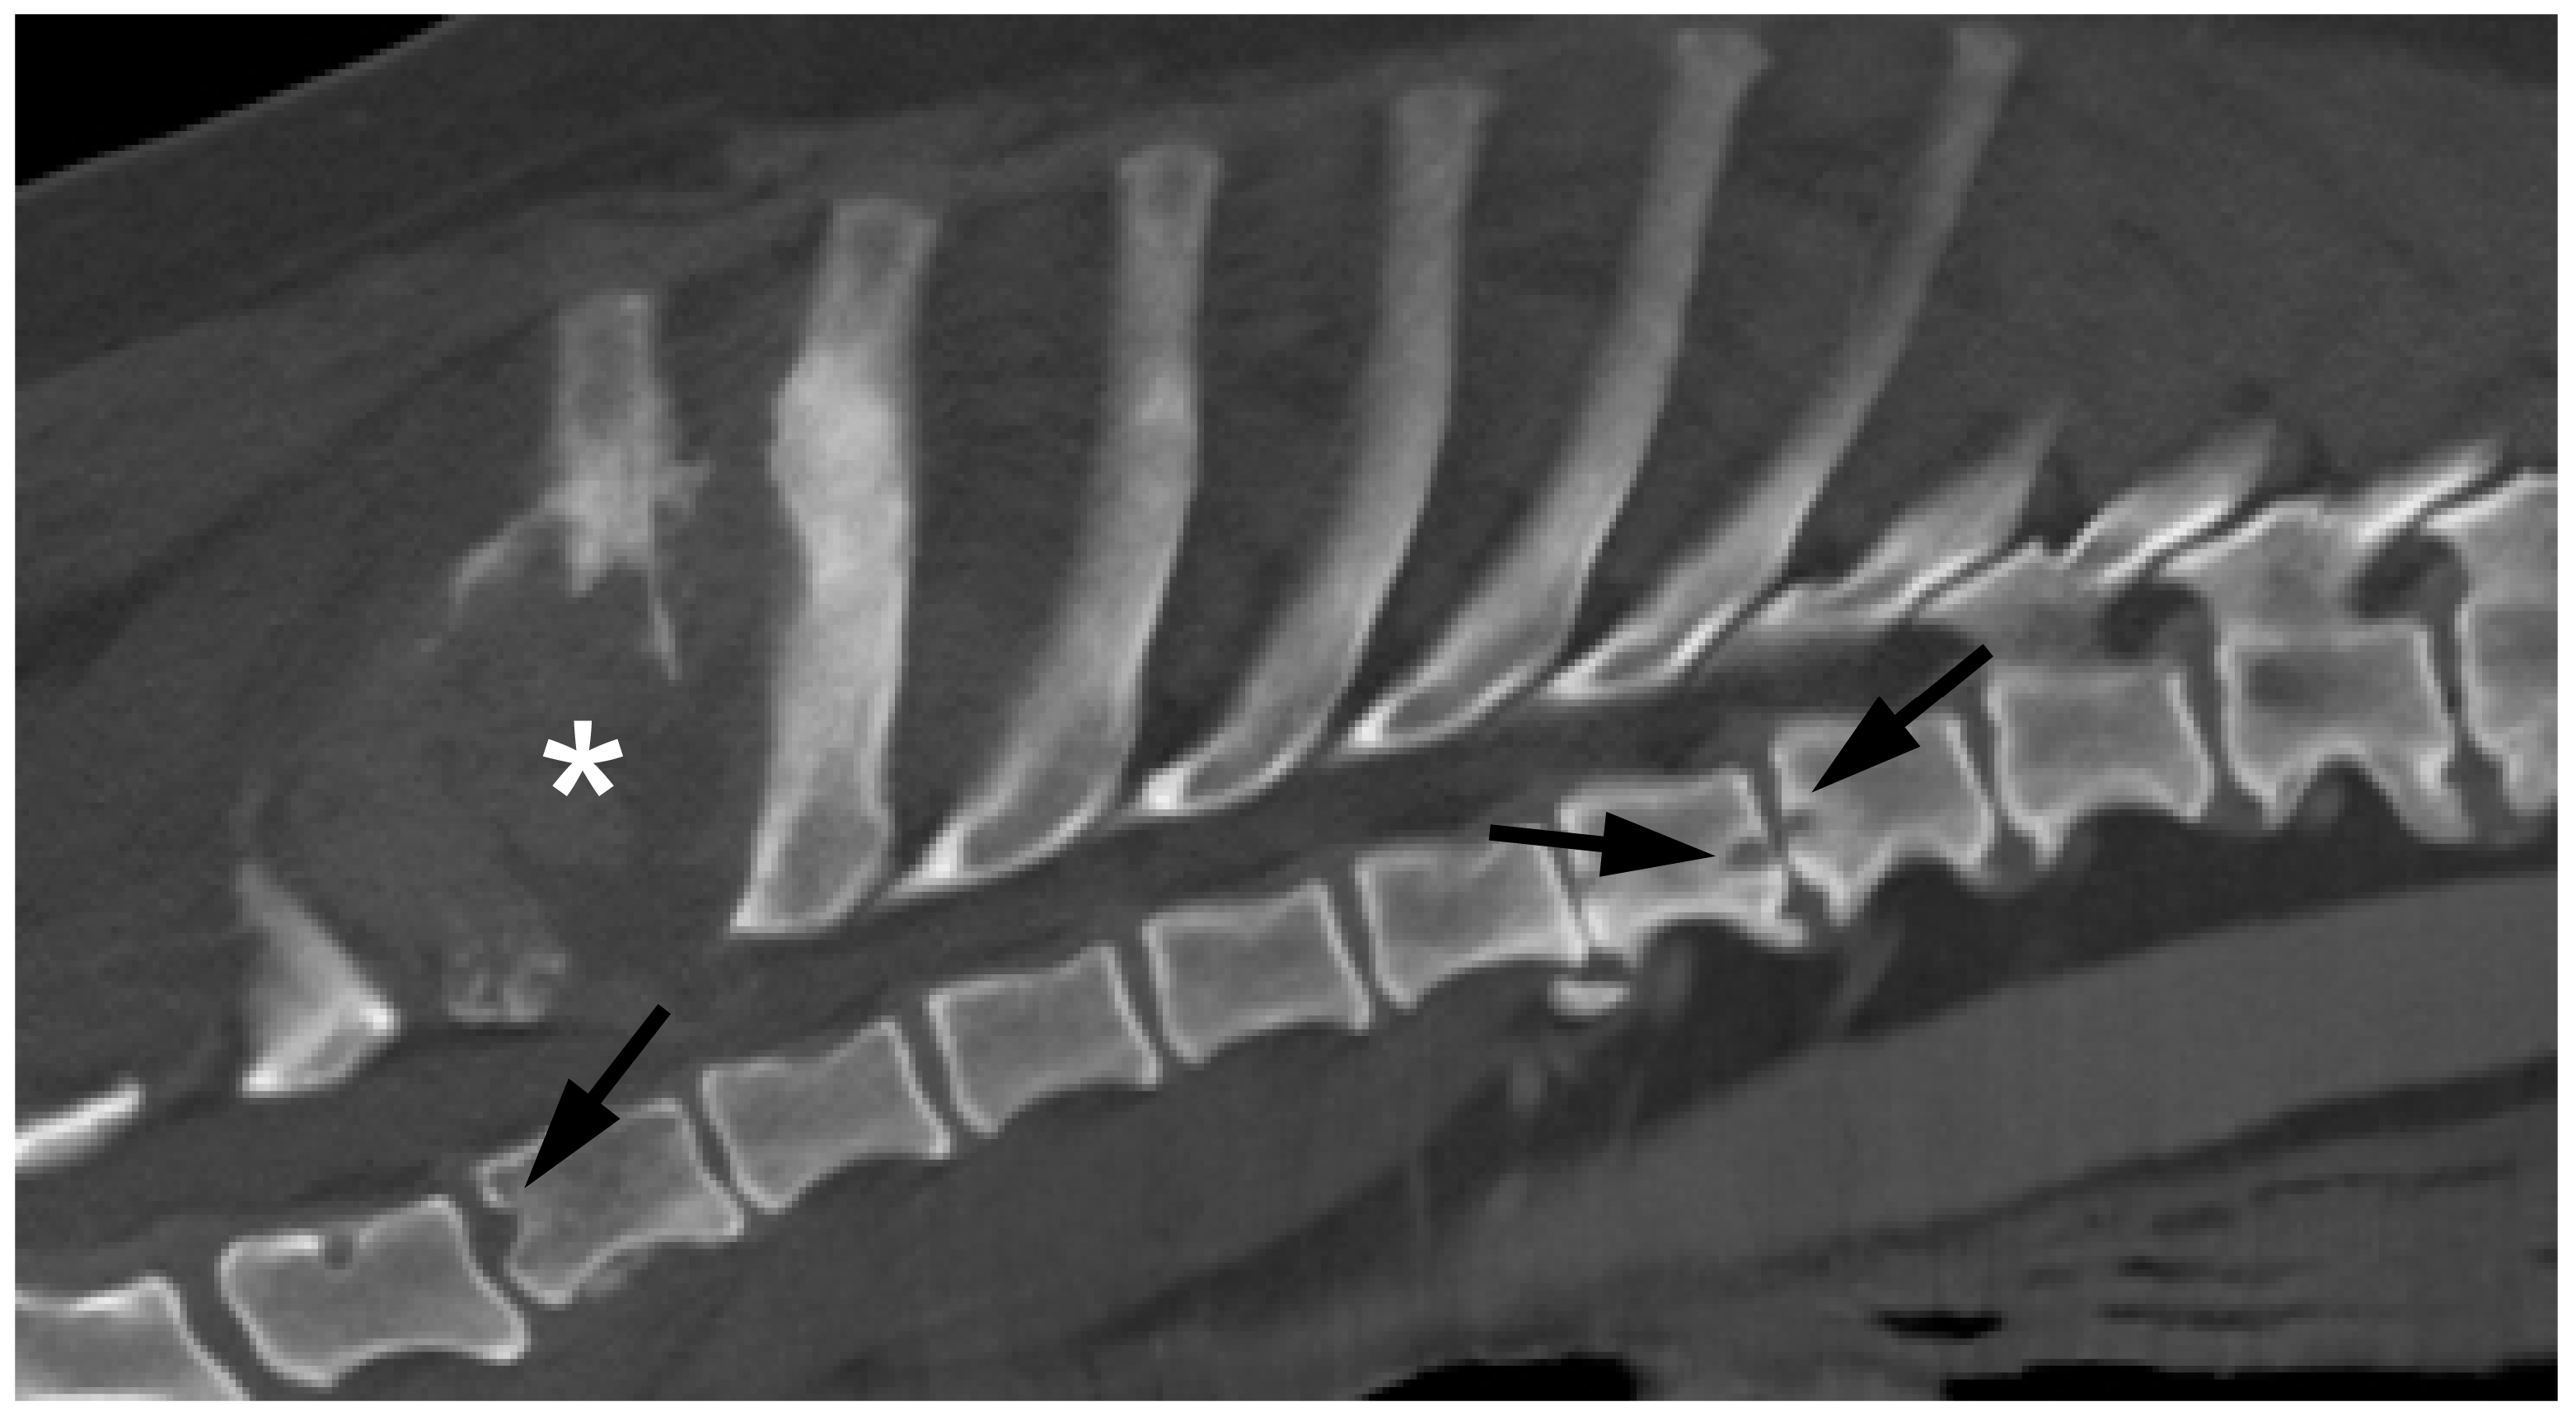

Of 37 dogs that had undergone blood cultures, 28 (76%) were positive (Table 1). Some dogs did not have blood culture performed because they had positive urine culture (n = 1), positive serology for Brucella canis (n = 3),or had undergone lesion sampling that detected an infectious cause (n = 4). Urine culture provided positive results in 12 of 39 tested [30%] dogs. Serology for antibodies to B.canis was submitted in 39 of these 45 dogs, and positive diagnosis of B. canis infection (i.e., positive culture, confirmatory positive testing after initial positive IFA test, or both) was made in 10, most commonly (7/10) from blood culture. A further seven dogs, which are included in the ‘imaging diagnosis only’ group below, showed a positive IFA test that was not supported by a positive confirmatory test. None of the dogs (n = 18) tested for B. suis/abortus were positive. In each of the Brucella canis-infected dogs, lesions on CT images were often small and smooth-edged, with a ‘flask’ shape of lysis surrounded by a thin rim of sclerotic bone (Figure 1).

Figure 1. CT and MR images of discospondylitis in a dog in which Brucella canis infection was diagnosed. (A) Parasagittal CT at the lumbosacral junction, showing a ‘flask-shaped’ erosion of the L7 vertebral body (arrow) and (B) transverse CT through the caudal aspect of L7 vertebra. Both images show bone loss with adjacent sclerosis (plus ventral spondylosis). (C) Mid-sagittal and (D) transverse T1-weighted plus contrast MR images at the same location. There is widespread contrast enhancement in (*) and around (arrows) the intervertebral disc.